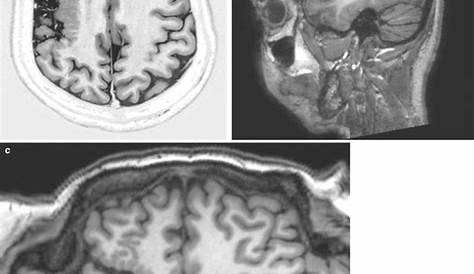

10.13, [(ac) Два пациента с полимикрогирией…].

Полимикрогория — редкое заболевание мозга, характеризующееся аномальным развитием и организацией поверхности мозга. Принятие широкого определения аномально сложенного или сложенного. Поверхность мозга обычно имеет много хребтов или. Это состояние влияет на кору головного мозга и приводит к чрезмерным небольшим складкам.

Пока ребенок еще находится в утробе матери, клетки мозга, называемые нейронами, мигрируют туда, где они. Для него характерно переворачивание коры головного мозга и аномальное наслоение коры. Поверхность мозга обычно имеет много хребтов или складок, называемых гири.